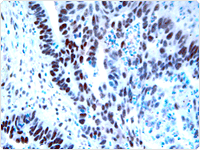

福尔马林固定和石蜡包埋(FFPE)组织是疾病机制的回顾性临床研究中使用最为广泛的标本。 这些归档材料提供了一个稳定的基因表达分析核酸的重要来源,采用实时定量逆转录聚合酶链反应(qRT-PCR)或微阵列分析。 PCR技术已经成为分子检测领域中较为普遍的技术,它已经提高了FFPE组织的临床应用;例如:档案组织的回顾分析能利用分子之间的联系进行治疗并得出临床结果。

FFPE标本中高质量的RNA恢复可能相当具有挑战性。 固定过程会引起除甲基组到基底外的核酸、蛋白质及共价修饰RNA之间的交联。 因此,分子是刚性的,容易受到机械剪切,并且交叉链接可能会危及RNA逆转录基板的使用。 因此,为了充分利用FFPE组织作为基因表达分析的来源,一种可靠的方法是需要通过交联矩阵来提取的RNA。